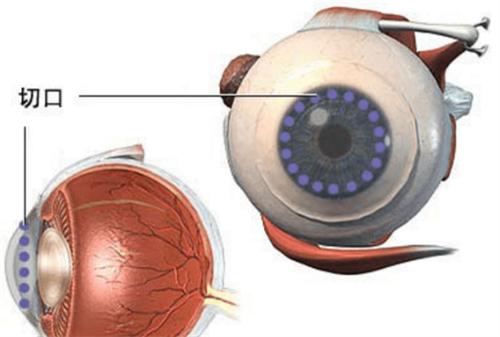

穿透性角膜移植:4.5万元起/单眼

适用人群:全层混浊或穿孔(如化学伤、溃疡)

含金量:飞秒激光辅助切口(精度0.1mm),术后散光降低40%

飞秒激光辅助比传统手术贵30%-50%,但精密度更高、改善更快